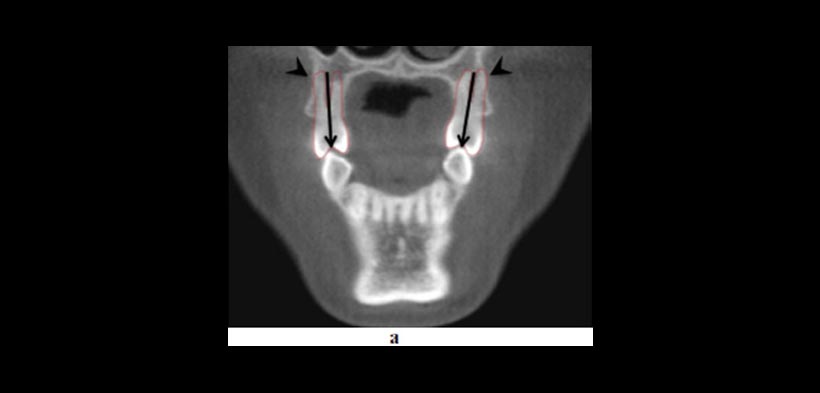

- EVALUACIÓN DE LA CALIDAD Y CANTIDAD ÓSEA: la determinación del volumen y la calidad del hueso, se han convertido en parámetros importantes en la prestación de tratamientos que usen dispositivos de anclaje (fig3).

Figura 3. La CBCT ofrece información sobre las condiciones de frontera que no son discernibles a partir de radiografías de rutina o durante el examen clínico, que pueden tener un impacto sobre las opciones de tratamiento. (a) Pre-tratamiento vista coronal que muestra la inclinación lingual (flechas) de los premolares maxilares y la proximidad de sus raíces bucales al margen de la cortical alveolar (puntas de flecha). (b) Post-tratamiento vista coronal que demuestra que las limitaciones ofrecidas por las condiciones de contorno relaciones hueso de la raíz se han abordado mediante torsión lingual de las raíces. (c) vista sagital y (d) vista transversal de la una CBCT de un individuo con limitaciones severas en las condiciones de contorno donde hay ausencia de corticales óseas. El tratamiento de ortodoncia estaría contraindicado en este caso.